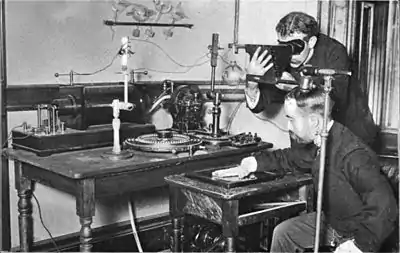

Fluoroscopy's origins and radiography's origins can both be traced back to 8 November 1895, when Wilhelm Röntgen, or in English script Roentgen, noticed a barium platinocyanide screen fluorescing as a result of being exposed to what he would later call X-rays (algebraic x variable signifying "unknown"). Within months of this discovery, the first crude fluoroscopes were created. These experimental fluoroscopes were simply thin cardboard screens that had been coated on the inside with a layer of fluorescent metal salt, attached to a funnel-shaped cardboard eyeshade which excluded room light with a viewing eyepiece which the user held up to his eye. The fluoroscopic image obtained in this way was quite faint. Even when finally improved and commercially introduced for diagnostic imaging, the limited light produced from the fluorescent screens of the earliest commercial scopes necessitated that a radiologist sit for a period in the darkened room where the imaging procedure was to be performed, to first accustom his eyes to increase their sensitivity to perceive the faint image. The placement of the radiologist behind the screen also resulted in significant dosing of the radiologist.

Red adaptation goggles were developed by Wilhelm Trendelenburg in 1916 to address the problem of dark adaptation of the eyes, previously studied by Antoine Beclere. The resulting red light from the goggles' filtration correctly sensitized the physician's eyes prior to the procedure, while still allowing him to receive enough light to function normally.